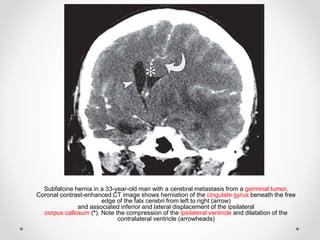

Subfalcine hernia in a 33-year-old man with a cerebral metastasis from a germinal tumor.

Coronal contrast-enhanced CT image shows herniation of the cingulate gyrus beneath the free

edge of the falx cerebri from left to right (arrow)

and associated inferior and lateral displacement of the ipsilateral

corpus callosum (*). Note the compression of the ipsilateral ventricle and dilatation of the

contralateral ventricle (arrowheads)

- Subfalcine hernia ina 33-year-old man with a cerebral metastasis from a germinal tumor. Coronal contrast-enhanced CT image shows herniation of the cingulate gyrus beneath the free edge of the falx cerebri from left to right (arrow) and associated inferior and lateral displacement of the ipsilateral corpus callosum (*). Note the compression of the ipsilateral ventricle and dilatation of the contralateral ventricle (arrowheads)